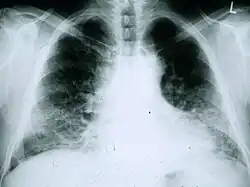

Thoraxfoto's zijn nuttig bij de vaste nacontroles bij IPF-patiënten. Zij zijn helaas niet geschikt voor diagnostiek, maar kunnen wel verminderde longvolumes zichtbaar maken, eventueel, in een gevorderd stadium, met prominente reticulaire interstitiële patronen nabij de longbases.[3]

Bij IPF is de radiologische evaluatie door middel van HRCT een essentieel onderdeel van het diagnostische traject. HRCT vindt plaats met een conventionele CT-scanner zonder injectie van contrastmiddelen. De te evalueren doorsnedes zijn altijd zeer dun (1–2 mm). Bij IPF zijn op HRCT-beelden van de thorax de kenmerkende fibrotische veranderingen in beide longen te zien, met name in de longbases en de periferie. Volgens de richtlijnen in de gezamenlijke ATS/ERS/JRS/ALAT 2011, is HRCT een essentieel onderdeel van het diagnostische traject bij IPF, waarmee UIP kan worden vastgesteld op grond van de aanwezigheid van:[2]

- Reticulaire verdichtingen, vaak samengaand met tractiebronchiëctasieën;

- Honingraatpatroon (‘honeycombing’), oftewel een cluster van luchthoudende cysteuze structuren met een duidelijke wand, doorgaans vergelijkbaar in diameter (3–10 mm) maar soms ook groter (tot 2,5 cm). Meestal subpleuraal gelegen en gevormd in ten minste twee lijnen. In het algemeen is één lijn van cysten niet voldoende om van een honingraatpatroon te kunnen spreken;

- Matglasverdichtingen komen vaak voor, maar zijn minder aanwezig dan de reticulatie;

- Kenmerkend is de basale en perifere locatie van de afwijkingen;